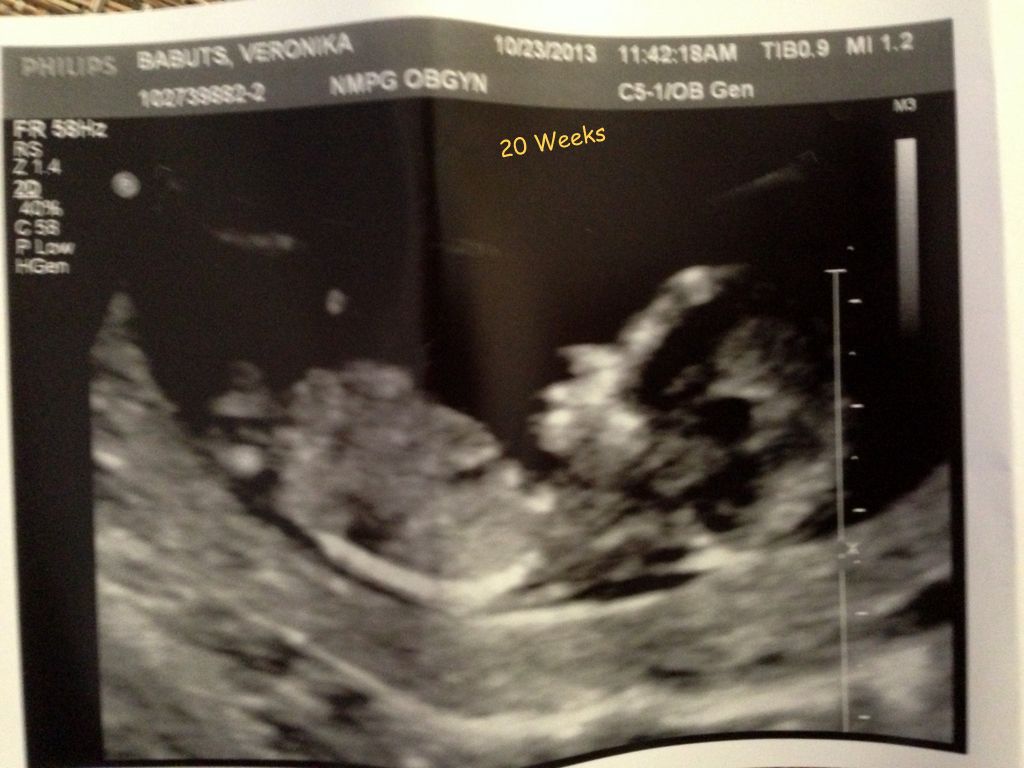

06.11.2014 - Grishka's First Days -- img_0259.jpg